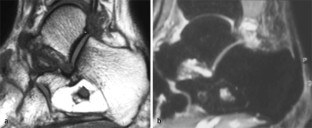

MRI morphology of bone tumors and tumor-like lesions

Für das Staging und die Charakterisierung von Knochentumoren und tumorähnlichen Läsionen ist in der Magnetresonanztomographie (MRT) der Einsatz von Spinechosequenzen erforderlich. Die MRT hat nur einen geringen Stellenwert in der Bestimmung der Dignität. Obwohl viele Knochentumoren und tumorähnliche Läsionen eine vergleichbare Morphologie in dieser bildgebenden Modalität aufweisen, können einige Tumorentitäten mittels MRT recht zuverlässig diagnostiziert werden. Hierzu zählen Knorpeltumoren, die solitäre und aneurysmatische Knochenzyste, der Riesenzelltumor, fetthaltige Läsionen und bis zu einem gewissen Grad auch das Osteoidosteom und das Osteoblastom. Es werden praktische Tipps gegeben, wann bei Tumorverdacht die MRT eingesetzt werden sollte, wie bei einem zufällig bei einer MRT gefundenen Tumor die Untersuchung modifiziert werden sollte und welcher Tumor vorliegen könnte.

Spin-echo sequences are mandatory at MRI for staging and characterization of bone tumors and tumor-like lesions. MRI is of minor value in the estimation of the malignant potential of an osseous lesion. Although many bone tumors and tumor-like lesions present similar morphology at MRI, some entities can be diagnosed with good reliability. These include chondrogenic tumors, solitary and aneurysmal bone cysts, giant cell tumors, lesions containing fatty tissue and, to a certain extent, osteoid-osteomas and osteoblastomas. Practical advice is given regarding when to perform a MRI study in cases of tumor suspicion. Further advices are given for cases a tumor is found incidentally at a MRI study, how to modify the study and which kind of tumor may be present.